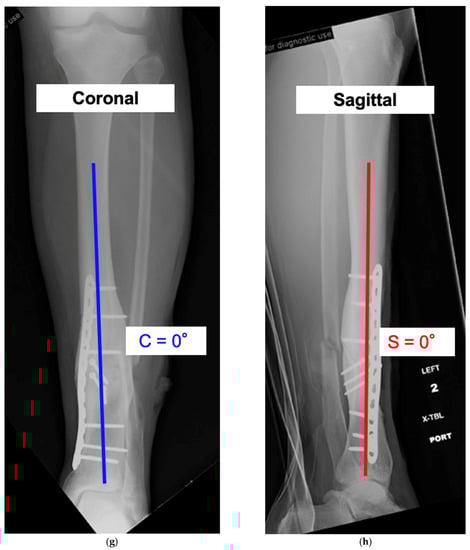

This is a case demonstrating the use of the mathematical charts to calculate the osteotomy angle and orientation. There was a tibial deformity of 22° varus in the coronal plane and a 0° deformity in the sagittal plane (Figure 8a,b). Because there was no deformity in the sagittal plane, the true angular deformity (A) was equal to the deformity in the coronal plane (C) and the orientation angle (α) was 0°. Based on a preoperative CT scan, the patient had a 15° internal rotational deformity (T = +15°). Variables A and T were used to calculate the osteotomy angle (θ = 56°) (Figure 8c). Variables α and T were used to derive the starting point angle (φ = +7.5°) (Figure 8d). To simultaneously correct the 22° angular deformity (A) and 15° rotational deformity (T), the osteotomy plane needed to be tilted 56° ascending (θ) and rotated 7.5° laterally (φ). Figure 8e,f show intraoperative fluoroscopic views of the osteotomy orientation before and after the correction. The osteotomy was made, then the distal segment was rotated until the bone was straight on both the coronal and sagittal views. Lag screw fixation with plate neutralization was done to achieve absolute stability. The final radiographs show the anatomic alignment in the coronal and sagittal planes (Figure 8g,h). In this particular case, there was a simultaneous correction of the coronal plane and internal rotational deformity without induced deformity in the sagittal plane.

Figure 8. See Case 2 description for details of a tibial malunion. (ah) calculate the variables θ (Osteotomy Angle) and φ (Starting Point Angle) to derive the mathematically directed osteotomy. Intraoperative and postoperative radiographs reveal successful correction of the deformity and osteotomy union.